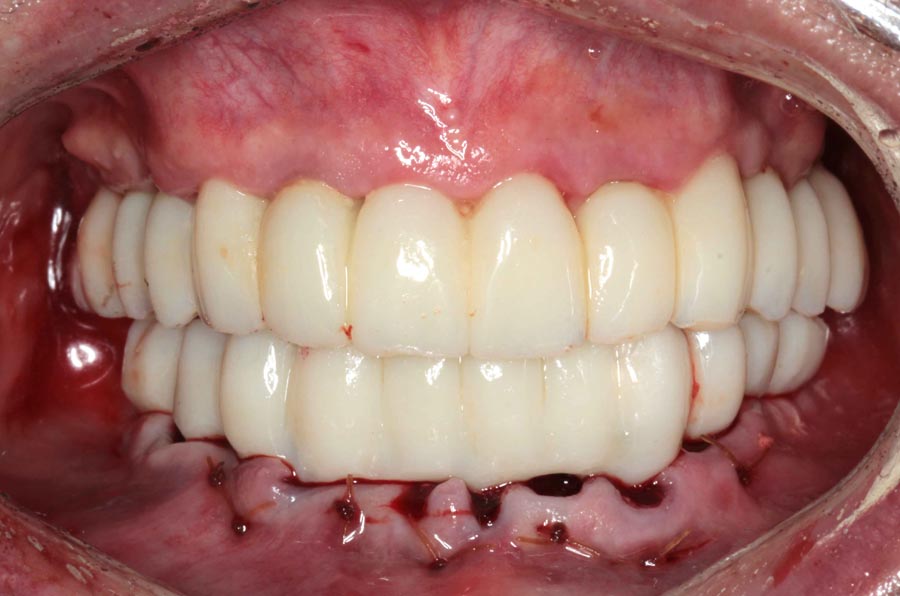

Final prostheses, intraoral, frontal. Homecare is still a problem. The final restorations are much kinder to the tissues and we hope this will resolve some of the inflammation.